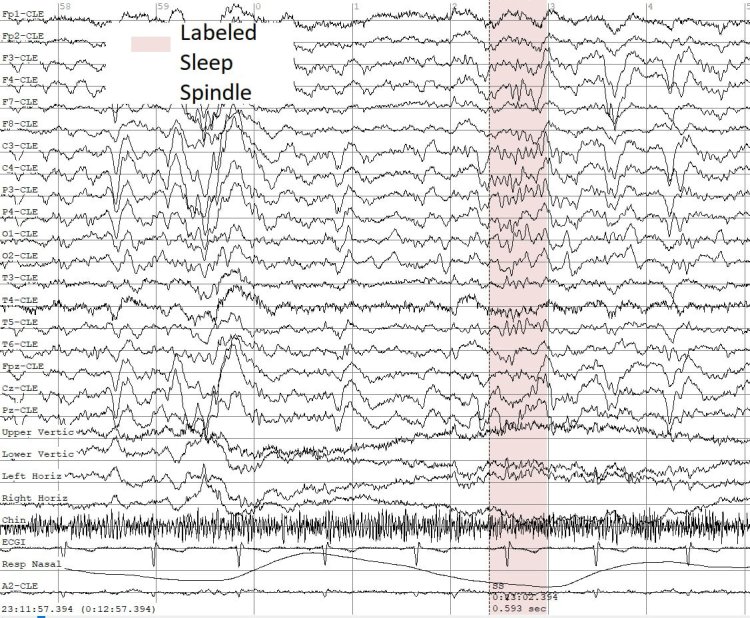

Пример паттернов сна (сонных веретен) в записях ЭЭГ. Иллюстрация предоставлена пресс-службой ННГУ

Один из ключевых этапов разработки был посвящён анализу нейросигналов второй фазы сна. Ритмы мозга, фиксируемые в этом состоянии у здоровых людей, называются «сонные веретёна». Они служат биомаркерами важнейших когнитивных процессов, таких как формирование долгосрочной памяти и усвоение новой информации. При эпилепсии характеристики сонных веретён (плотность, частота, длительность) могут нарушаться, и их автоматический анализ может служить важным биомаркером течения болезни при уже установленном диагнозе. Метод нижегородских учёных позволяет описать и проанализировать эти изменения.